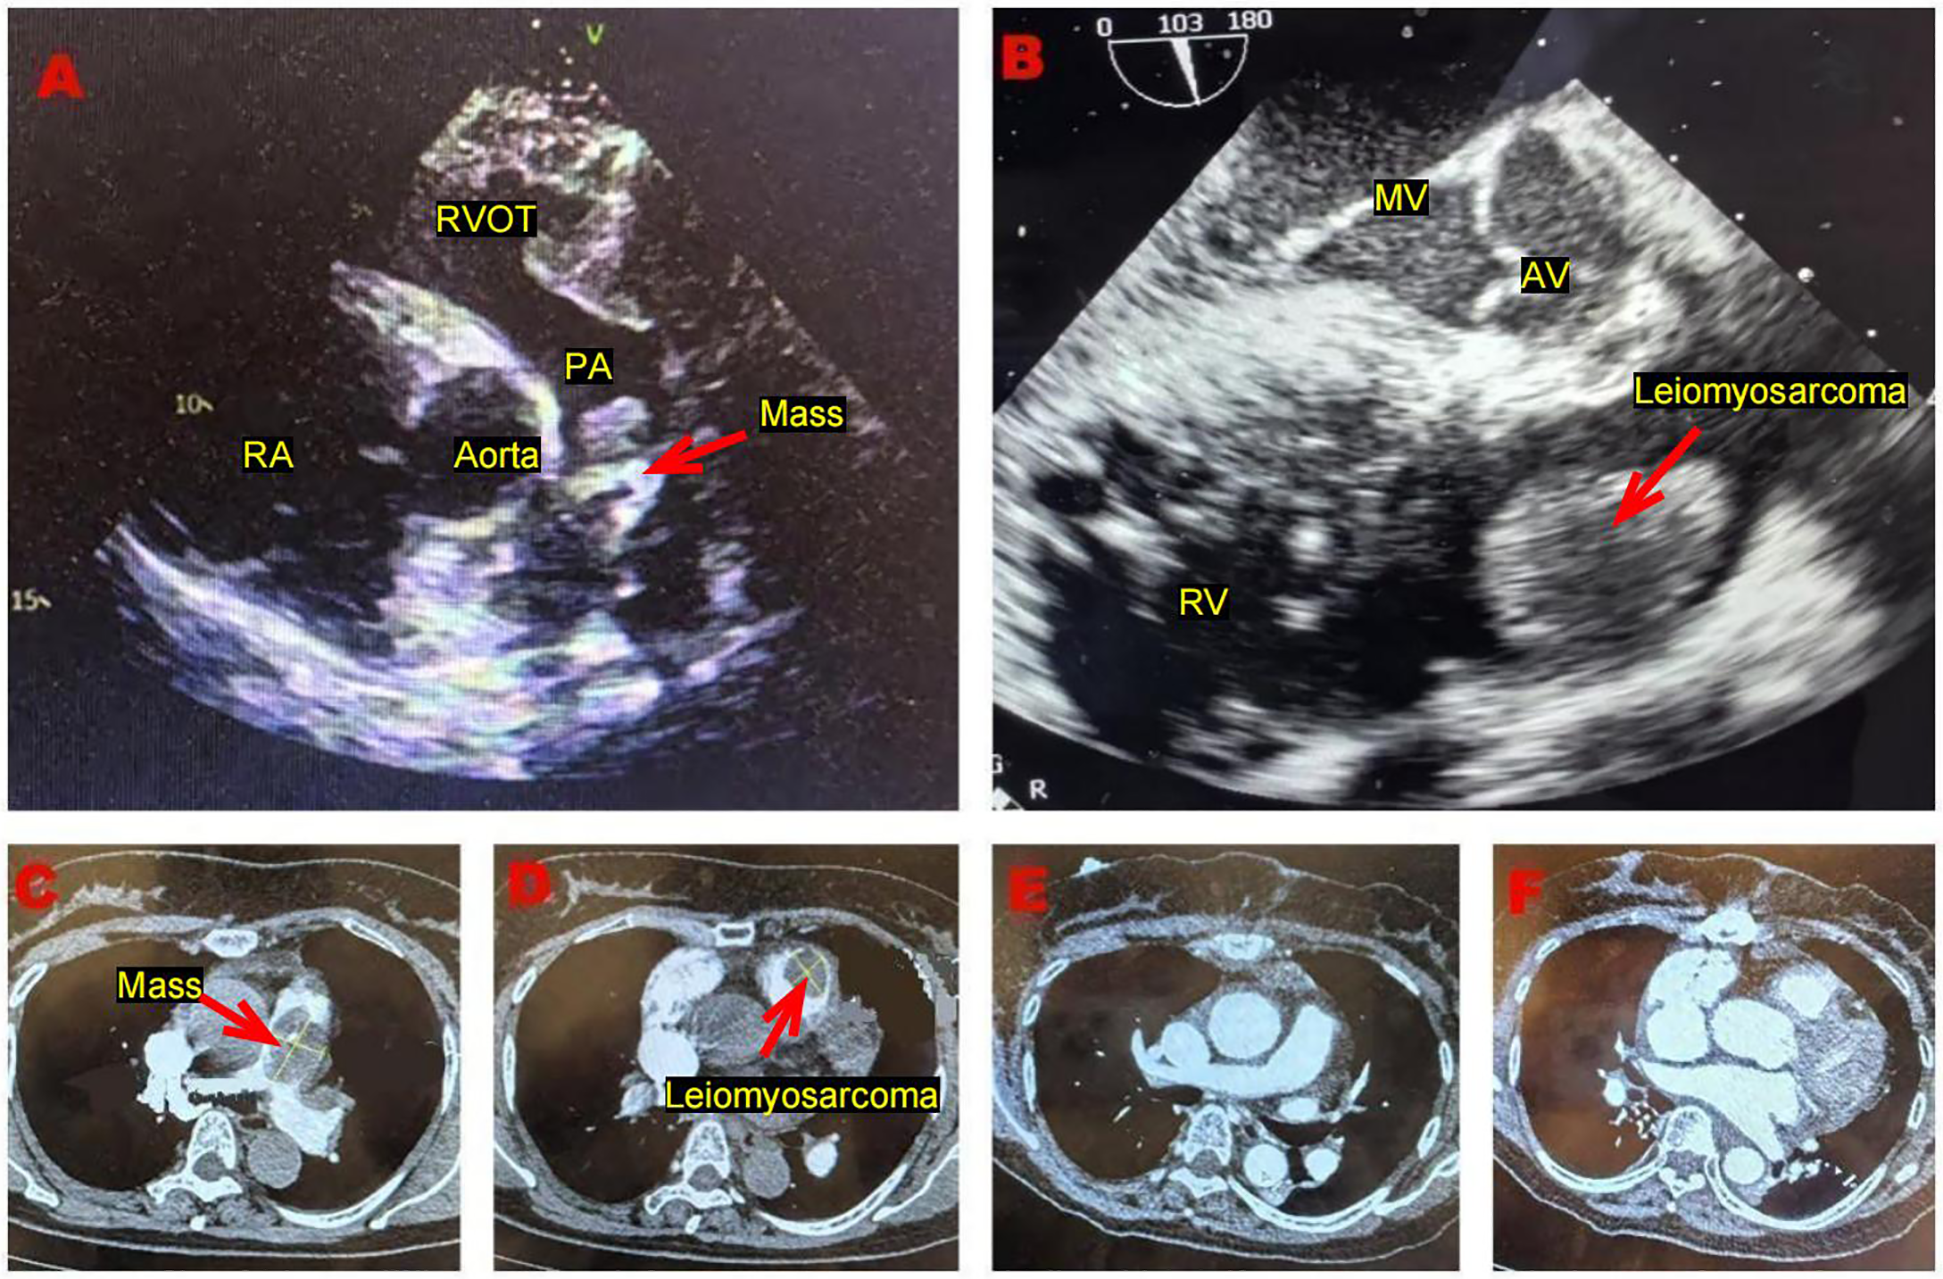

A 61-year-old female presented to our hospital with dyspnea and eyelid edema. Approximately three months prior, she experienced similar symptoms at a regional medical facility, where a computed tomography (CT) scan revealed a pulmonary embolism. An attempt at interventional thrombectomy was made, but it was ultimately unsuccessful. Nevertheless, the patient's symptoms showed significant improvement compared to their initial presentation. Following the procedure, she was started on oral anticoagulation therapy with rivaroxaban tablets. Five days before admission, the patient again experienced shortness of breath and notable eyelid edema after physical activity, leading her to seek medical attention at our hospital. Upon admission, a physical examination indicated a body temperature of 36.5°C, blood pressure of 138/79 mmHg, pulse rate of 70 beats per minute, respiration rate of 20 breaths per minute, blood oxygen saturation of 99%, and no murmurs detected during cardiac auscultation. Additionally, a lower limb vascular ultrasound revealed no signs of thrombosis. The pulmonary artery CT angiography (CTA) revealed a patchy filling defect in the main pulmonary artery, measuring approximately 4.8 × 2.7 cm, indicative of a significant area of embolism. Additionally, a filling defect of 2.5 × 2.0 cm was identified in the right ventricle, raising concerns for thrombosis. Echocardiography (Figure 1) demonstrated an isoechoic mass approximately 2.5 × 2.2 cm in size located in the right ventricular outflow tract, alongside an irregular isoechoic mass measuring around 3.8 × 1.8 cm in the pulmonary artery (Figure 1A). A cord-like hyperechoic mass was observed within the latter, oscillating in conjunction with the cardiac cycle. Color doppler flow imaging (CDFI) revealed a filling defect in the pulmonary artery, accompanied by a high systolic peak velocity of 2.8 m/s and severe tricuspid regurgitation. The estimated pulmonary artery pressure was approximately 31 mmHg, and the electrocardiogram displayed sinus rhythm. In our laboratory testing, we measured D Dimer levels at 1.39 µg/ml (0.00–1.00 ug/ml) and recorded brain natriuretic peptide (BNP) levels at 5,524.54 pg/ml (0–120 pg/ml). Blood gas analysis indicated an oxygen partial pressure of 118 mmHg. Initially, we considered the potential presence of a tumor, which could not be ruled out. Consequently, we conducted a tumor marker examination, revealing CA199 levels of 42.73 U/ml (0.00–35.0 U/ml) and CA125 levels of 52.94 U/ml (0.00–30.0 U/ml). Given the critical risk of thrombus detachment at any moment, we proceeded with emergency surgery.

Figure 1

(A) Transthoracic echocardiography, performed in the short-axis view of the aorta, demonstrates an irregular isoechoic mass, situated within the main pulmonary artery. (B) Transesophageal ultrasound reveals an isoechoic mass with a regular shape situated in the atypical region of the right ventricular outflow tract. This mass appears to be connected to the anterior wall of the right ventricle via a pedicle. (C) Pulmonary artery computed tomography angiography reveals a patchy filling defect in the main pulmonary artery. (D) Pulmonary artery computed tomography angiography reveals a filling defect in the right ventricle outflow tract. (E,F) The postoperative pulmonary artery computed tomography angiography indicates no signs of residual tumor.

The treatment of cardiac leiomyosarcoma involves a variety of approaches, including surgery, radiation therapy, chemotherapy, targeted therapy, and immunotherapy. Currently, surgical tumor resection is the only treatment modality shown to effectively eradicate this disease and improve survival rates (23). Literature (24) indicates that the average survival time for patients who do not undergo surgery ranges from 6 to 12 months, while those who receive surgical intervention have an average survival time of approximately 24 months. Pathological examination confirmed the diagnosis of cardiac leiomyosarcoma in this patient. Postoperative pulmonary artery computed tomography angiography (Figures 1E,F) and cardiac ultrasound revealed unobstructed blood vessels and no abnormalities in the cardiac chambers. Furthermore, a whole-body positron emission tomography-computed tomography (PET-CT) scan was performed to check for metastatic tumors. Fortunately, no tumors were detected in other organs, and no residual tumor was found in the cardiac chamber, resulting in an R0 resection. Currently, the adjuvant treatment options following cardiac leiomyosarcoma surgery remain uncertain. For metastatic or unresectable leiomyosarcoma, the primary treatment regimen remains anthracycline-based chemotherapy, with doxorubicin serving as the most representative agent. Doxorubicin operates by inhibiting topoisomerase II and inducing oxidative stress, which leads to DNA damage. Karavelioglu et al. (25) reported a case involving an 86-year-old female patient diagnosed with epicardial leiomyosarcoma, presenting as cardiac tamponade. She was administered doxorubicin at a weekly dose of 25 mg/m2 for five months without surgical intervention, and she continued to survive, suggesting that this treatment was both safe and effective. In contrast, Sachdev et al. (26) noted that the benefits of doxorubicin are limited by dose-dependent adverse effects, particularly cardiotoxicity, which typically occurs when the cumulative dose exceeds 550 mg/m2. One proposed mechanism underlying this cardiotoxicity is the conversion of doxorubicin into its active metabolite, doxorubicinol. Therefore, it is essential to pursue the development of novel delivery methods aimed at reducing this toxicity. One such method involves the use of albumin ligands to create a prodrug form of doxorubicin, known as aldoxorubicin. This prodrug consists of the C-13 section of doxorubicin combined with a blend of six equine sources and is synthesized through the reaction between imidocaproic acid and hydrazine. In the bloodstream, the maleimide component forms a covalent bond with Cys34 of albumin. Upon exposure to the acidic environment of tumors, the hydrazone ligand degrades, resulting in the release of doxorubicin. An international, multicenter, phase 2b, open-label, randomized study (27) enrolled 123 patients with untreated locally advanced or unresectable disease, assigning them to either an aldoxorubicin group (n = 83) or a doxorubicin group (n = 40). The median progression-free survival was significantly greater in the aldoxorubicin group, with a median of 5.6 months (95% CI, 3.0–8.1), compared to 2.7 months (95% CI, 1.6–4.3) in the doxorubicin group (P = 0.02). Furthermore, the monthly progression-free survival rate was superior in the aldoxorubicin group, recorded at 46% vs. 23% in the doxorubicin group (P = 0.02). The median overall survival was reported as 15.8 months (95% CI, 13.0 to unavailable) for the doxorubicin group and 14.3 months (95% CI, 8.6–20.6) for the aldoxorubicin group (P = 0.21). No acute cardiotoxic effects were observed with either treatment. However, three patients receiving doxorubicin exhibited a left ventricular ejection fraction of less than 50%, suggesting that doxorubicin alone may prolong progression without improving survival. Improvements in 6-month progression-free survival and tumor response rates were found to be superior with aldoxorubicin, indicating its promising therapeutic potential. However, since the drug remains in the research stage and the available literature is relatively limited, further clinical studies may be necessary in the future to validate its efficacy. Additionally, there are related reports (28–30) concerning combined drug chemotherapy. Tap et al. (31) evaluated the efficacy of doxorubicin combined with a placebo vs. doxorubicin combined with olaratumab in the treatment of advanced sarcoma through a randomized controlled trial. The conclusion indicated no significant difference in overall survival between the two treatment regimens. Given the potential for cardiac toxicity, we plan to administer low-dose doxorubicin alone for subsequent treatment. The specific regimen will involve 25 mg/m2, administered weekly over a course of 4 weeks, for a total of 8 cycles. Throughout the treatment process, we will closely monitor for possible adverse reactions, including cardiotoxicity, bone marrow suppression, and gastrointestinal reactions, adjusting the treatment plan as necessary based on the patient's specific circumstances. We have communicated with the patient multiple times, providing comprehensive medical explanations and psychological counseling; however, the patient has declined to accept subsequent standardized treatment. Consequently, we were unable to obtain follow-up data for further treatment, which poses limitations to this study.